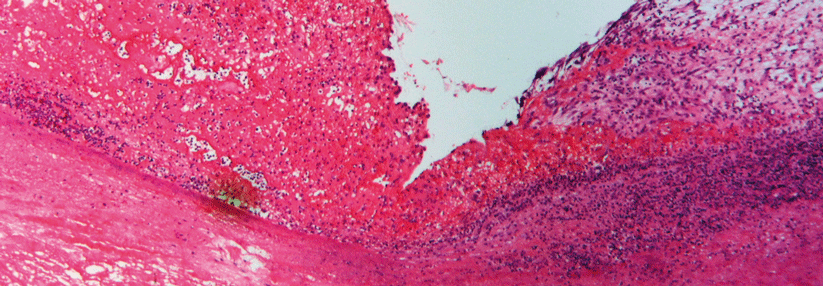

In diesem Fall haben Streptokokken eine Herzklappe befallen. Oft sind auch weitere Strukturen betroffen. In diesem Fall haben Streptokokken eine Herzklappe befallen. Oft sind auch weitere Strukturen betroffen. © Science Photo Library/Christol, D. / CNRI

Die Keime können viele Strukturen am Endokard befallen, vom Klappensegel bis hin zur Schrittmachersonde, kombiniert oder einzeln (s. Kasten). Ungefähr in 70 % der Fälle lässt sich in der Echokardiografie eine Vegetation nachweisen. Wie aber verfährt man bei den 30 %, bei denen sich im Echo nichts findet? Laut einer Studie, in der alle Teilnehmenden eine kontinuierliche Bakteriämie aufwiesen, ändert die negative Bildgebung nichts an der Prognose. „Das heißt, die Echokardiografie alleine sollte nicht dazu dienen, eine Endokarditis ausschließen zu wollen“, sagte Prof. Mangner. Man brauche einen multimodalen Ansatz, der Bildgebung, Mikrobiologie und Klinik beinhaltet.